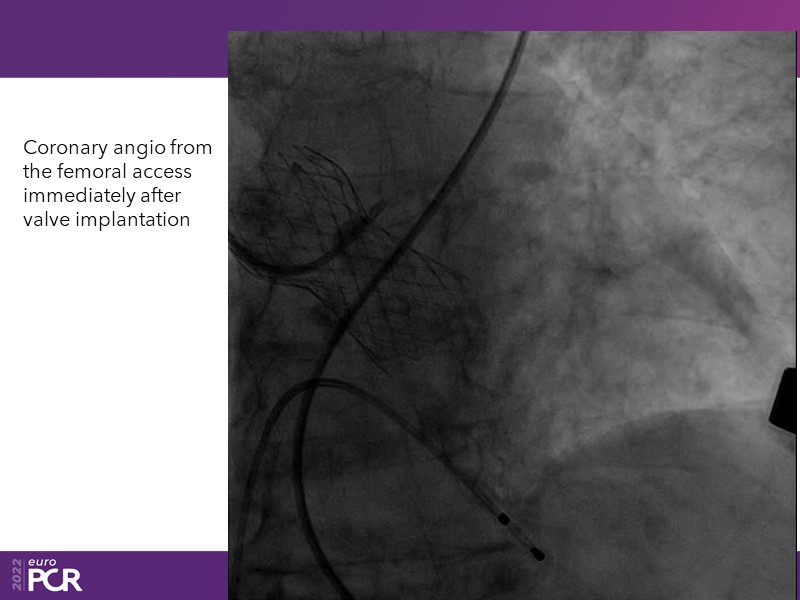

Consult this session to learn how to contribute to streamlined pre- and post-TAVI patient pathways, to discover updates on the optimised TAVI procedure and appreciate the variances in different valve designs and the long-term patient outcomes, as well as to discuss the right time of PCI in TAVI patients (steps on the procedure).